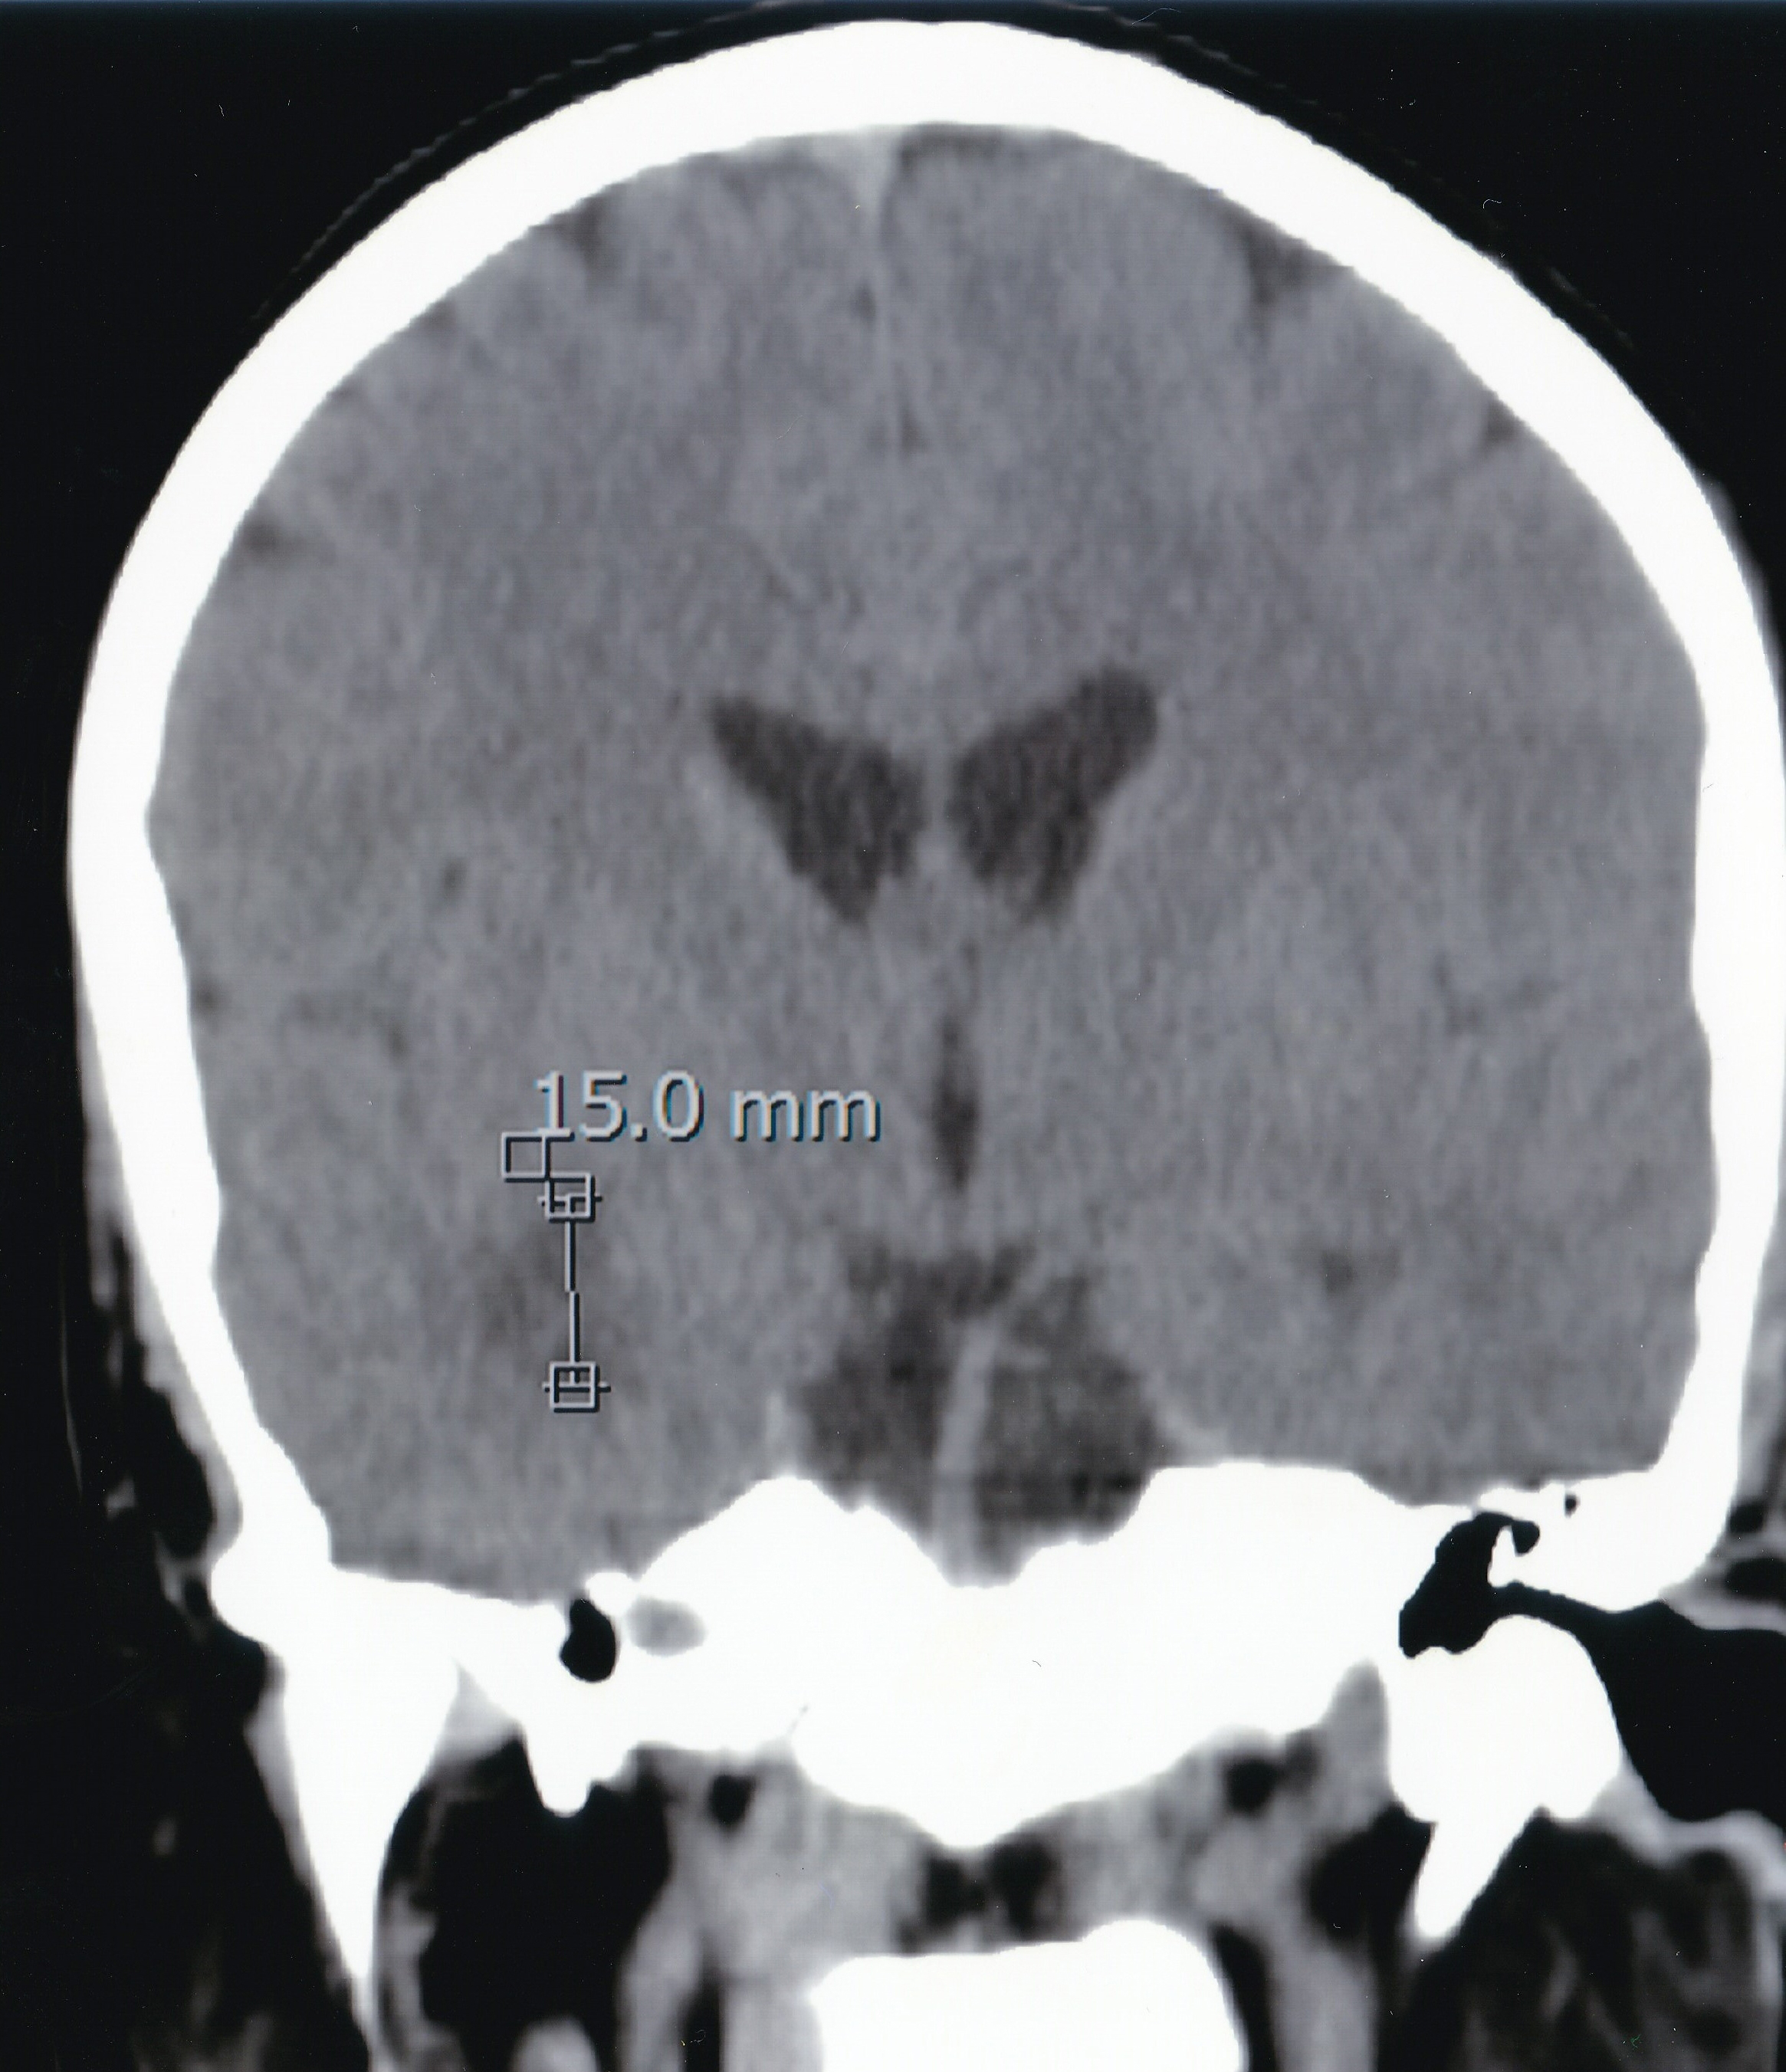

Retinitis can be caused by a number of reasons, namely infectious or autoimmune, and the correct diagnosis is fundamental in order to provide the best treatment and to prevent irreversible visual loss. We report a case of a young healthy man who presented with bilateral multifocal retinitis with perilesional vascular involvement following a febrile period and a cutaneous rash. Despite some initial pitfalls, a diagnosis of Rickettsia conorii was finally made and appropriate treatment was provided. To our knowledge, this is one of the few reported cases of posterior uveitis due to rickettsiosis in which rare ocular complications are seen, including bilateral macular edema with foveal detachment and macular star development, and in which treatment with systemic corticosteroids was provided due to sight-threatening lesions.